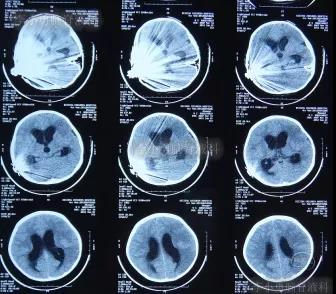

一到第3家医院,就开展了急诊气管插管和之后呼吸机辅助呼吸的抢救。住院次日,即2012年5月17日,脑CT检查并未发现明显异常(图-3)。

图-3:2012年5月17日耳蜗植入术后状态脑CT